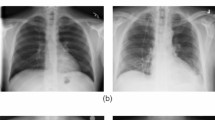

Deep learning (DL) is a branch of machine learning (ML) which is inspired by the way the human brain works and utilized for feature extraction as well as classification of images. Main strength of DL is that it is an unsupervised learning i.e., it can learn from unlabeled data. DL has been vastly used in industries, self-driven cars, face recognition, object detection, image classification, etc. [43] due to characteristics like unlabeled data utilization, working without feature engineering, prediction with high accuracy and precision. Convolutional neural network (CNN) is a DL algorithm that has been used extensively in solving problems like document analysis, different types of image classification, pose detection, and recognizing various actions [44]. Medical imaging is one of the areas where CNN has been showing encouraging results [45], and thus, convolutional neural networks (CNNs) have been doing well in detecting several diseases like coronary artery disease, malaria, Alzheimer’s disease, different dental diseases, and Parkinson’s disease. Likewise, CNN has considerable prospects for differentiating COVID-19 from non-COVID-19 infections with medical images like chest X-rays and CTs using public databases of chest X-rays and CTs. The chest X-rays and CT scans of COVID-19 positive cases and normal are presented with the help of Fig. 2.